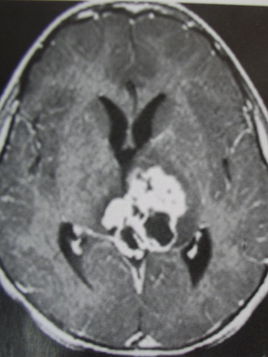

顱內(nèi)生殖細胞瘤是臨床上比較少見的一種惡性腫瘤,發(fā)病率在3.5%左右,多見于青少年群體以及兒童,在老年人群以及幼兒中較為罕見,好發(fā)部位是鞍區(qū)以及松果體區(qū),在丘腦、基底節(jié)部位較為少見,生殖細胞瘤極易導(dǎo)致腦脊液散播種植,并對周圍的結(jié)構(gòu)進行侵犯,早期精確、有效的診斷對于患者疾病的治療具有十分重要的意義。